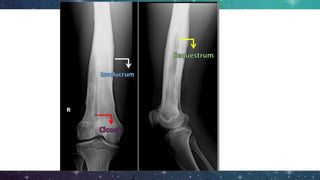

- Pieces of necrotic bone can separate known as

sequestrum (containing pus)

- New bone formation known as involucrum

Imaging

● Plain film radiography

○ Extend at least 1cm/ compromise 30 -

50% of bone mineral

○ Bone destruction may not appear until

approximately 2 weeks after onset

○ Osteolysis, periosteal reaction and

sequestra

○ Brodie’s abscess